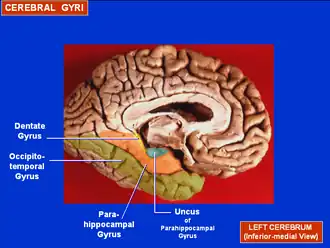

Visão medial do hemisfério cerebral esquerdo (giro para-hipocampal em laranja).

Superfície medial do hemisfério cerebral esquerdo. Giro para-hipocampal mostrado em laranja.

Superfície medial do hemisfério cerebral esquerdo. Giro para-hipocampal mostrado em laranja. -